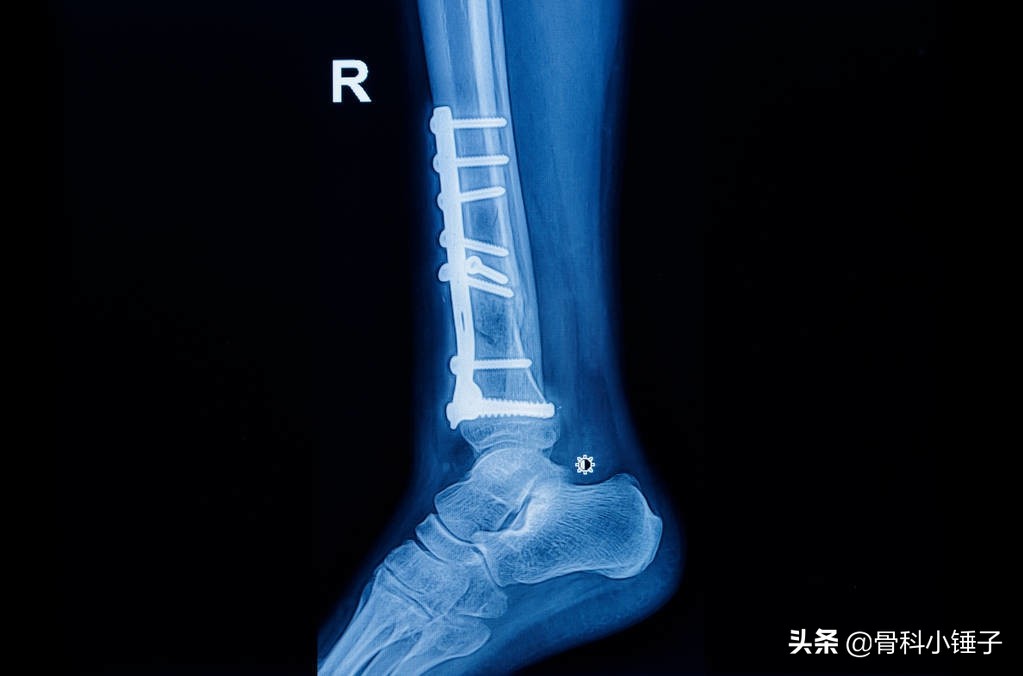

1.腓骨骨折固定方式:3.5mm钢板、拉力螺钉、可吸收钉、克氏针张力带等。

考虑问题:中上段骨折是否处理?钢板?克氏针?旷置?

关键看腓骨长度旋转是否纠正,直接影响下胫腓联合是否稳定。

2.腓骨长度和旋转的恢复

术中判断:患侧X线透视、距小腿角是否恢复、必要时双侧对比